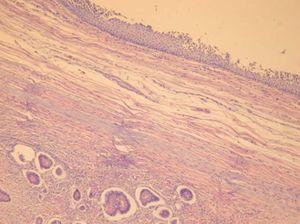

En el estudio microscópico de la zona sólida (fig. 3) encontramos una neoformación epitelial con claros carácteres «insulares». Los grupos neoformativos se disponen en islotes de tamaño medio y pequeños muy bien definidos, con celularidad redondeada con núcleos hipercromáticos, isonucleosis, isocariosis y escasa mitosis. Estos islotes presentan luces alrededor de las cuales se distribuyen en forma de empalizada de células cuboidales o cilíndricas. En otras zonas, la neoformación adopta una disposición glanduloide, mezclada con el tejido insular descrito que muestra en esta zona criterios de atipia nuclear y celular más acentuada (fig. 4).

Figura 4.Tumor carcinoide, con islotes patrón insular típico (HE, ×400).